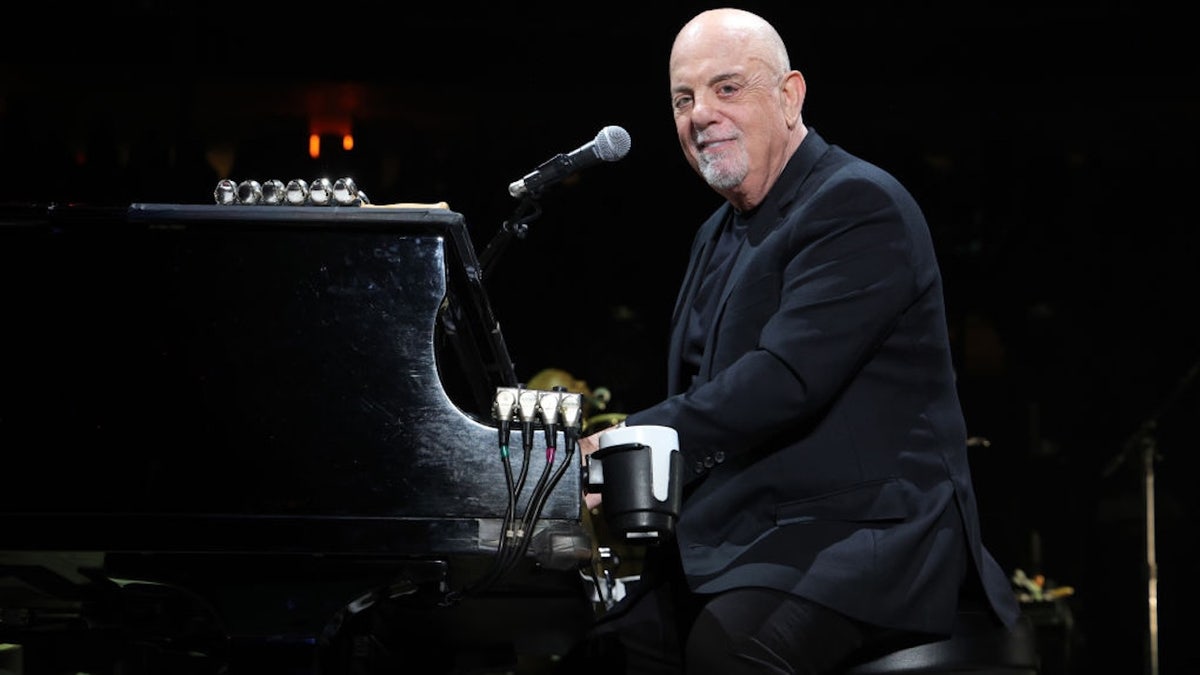

Normal pressure hydrocephalus is a version of the condition that is typically seen in older people, where the cerebrospinal fluid builds up without increasing the pressure in the brain.

Despite the fact that pressure remains normal, NPH can impact brain function, particularly the areas of thinking, memory, movement and focus, according to Cleveland Clinic.

The three main effects of NPH are gait issues, urinary incontinence and cognitive difficulties. Collectively, these symptoms are known as “Hakim’s triad.”

The cognitive problems can include memory loss, slow thinking and difficulty, according to Mia Kazanjian M.D., a board-certified radiologist in private practice based in Connecticut.

The five-time Grammy winner, 76, announced on Friday that he has normal pressure hydrocephalus (NPH), which occurs when cerebrospinal fluid builds up inside or around the brain. (Kevin Mazur/Getty Images)

“This can negatively impact someone’s career and personal life, limiting the ability to do activities of daily living like eating, bathing and dressing,” Kazanjian, who was not involved in the study, told Fox News Digital. “This can also lead to emotional changes, like depression.”

Urinary incontinence means loss of bladder control, which can cause discomfort, anxiety and embarrassment, according to the doctor.

“This can predispose someone to bladder infection and skin irritation,” she cautioned. “If someone has to get up in the middle of the night due to this, he or she is more likely to fall. Furthermore, it can lead someone to isolate socially, which can lead to feelings of loneliness.”

Gait impairment means the person’s steps are unsteady, there is loss of balance, and feet can stick to the ground, shuffle or freeze, Kazanjian said.

“The danger is that someone can fall and sustain trauma with a significant injury,” she warned.

The condition can often be mistaken for dementia, but some cases of NPH can be treated and reversed.

The only known risk factor for NPH is age, Cleveland Clinic noted, with the average age of onset around 70.

Approximately 0.2% of people between 70 and 80 will develop NPH, and it affects around 5.9% of those over 80, the above source stated.

Only around 0.003% of people under 65 will get the condition.

“About 30% of people with NPH also have Alzheimer’s disease or a similar degenerative brain disease,” Cleveland Clinic states.